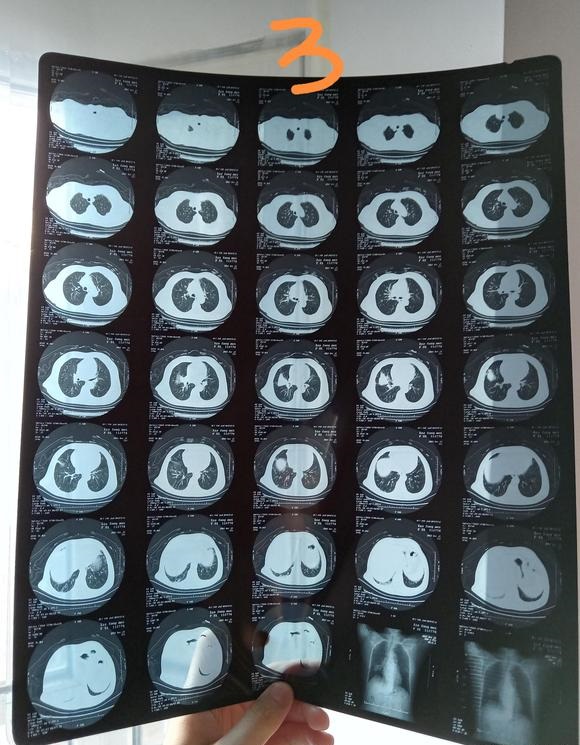

北港永下 02021-12-21 患者家属我父亲体检时发现有肿块。到人民医院检查结果显示食管囊肿或支气管囊肿本来医生说不是很大的手术。几天前做了增强ct。又说有可...